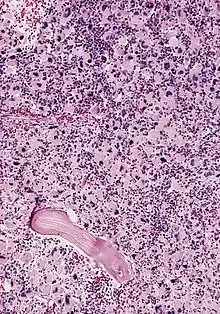

Acute megakaryoblastic leukemia

AML-M7, bone marrow section